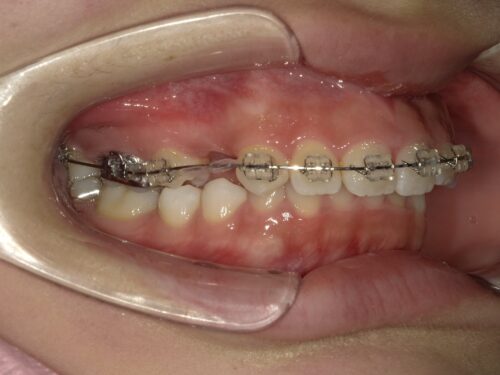

ワイヤー装着後・左側の写真

ワイヤー装着後・右側の写真

左右それぞれの側面です。ブラケットにワイヤーが通っているのが見えますね。